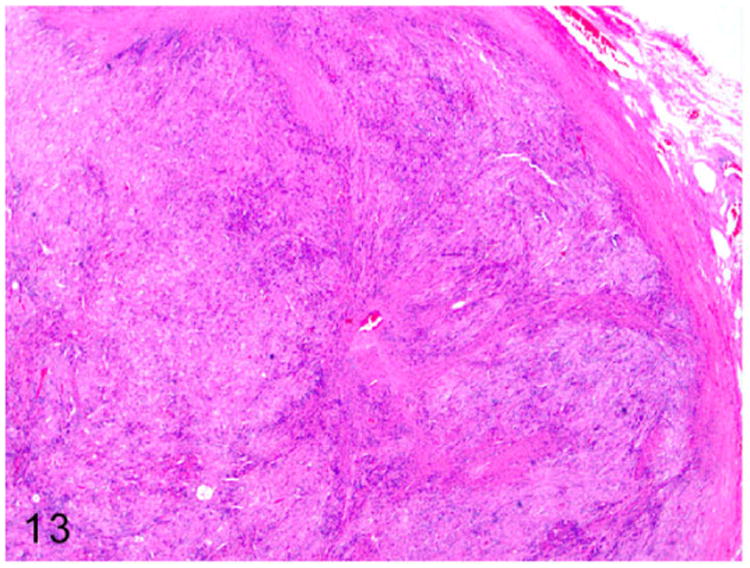

Grossly, these steroid-producing neoplasms are yellow to orange due to the intracytoplasmic lipid vacuoles.84 Histologically, the ovarian architecture is completely effaced and replaced by the lobulated expansile mass (Fig. 13). The biphasic neoplasm is predominantly composed of spindle cells and polygonal cells that are supported by dense fibrous connective tissue (Fig. 14). The spindle shaped neoplastic cells are frequently arranged in interlacing fascicles, have indistinct cell borders, moderate amount of eosinophilic cytoplasm, and elongated nuclei. The polygonal neoplastic cells are arranged in cords forming tubule-like structures, have vacuolated cytoplasm, and round to oval nuclei with prominent nucleoli. Sex-cord stromal tumors can be characterized and differentiated from smooth muscle neoplasms based on their positive immunoreactivity to markers such as calretinin and inhibin-α.

Figure 13.

Sex-cord stromal tumor, ovary, ferret. Ovarian architecture is effaced by a lobulated highly cellular spindle cell neoplasm supported by dense fibrous connective tissue. HE.